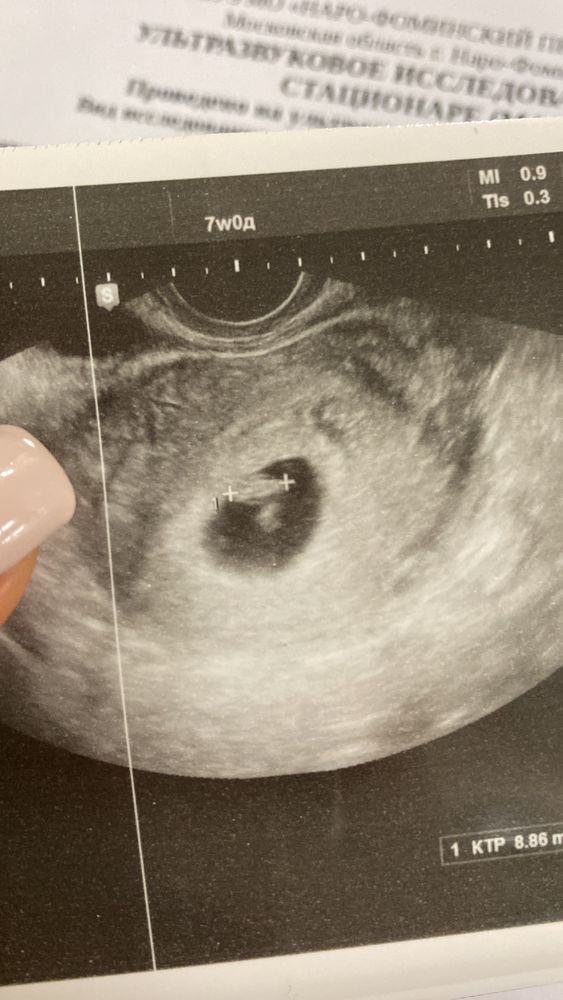

Annie, ещё если у вас есть узи на раннем сроке, можно тоже предположить) если есть, скиньте сюда (6-7-8 недель)

Enotik Lesnoy , Изображение

Annie, в общем-то, я думаю, что у вас мальчик. По форме лба на скрининге, по расположению хориона (плаценты) на этом узи.. но посмотрим, время покажет)